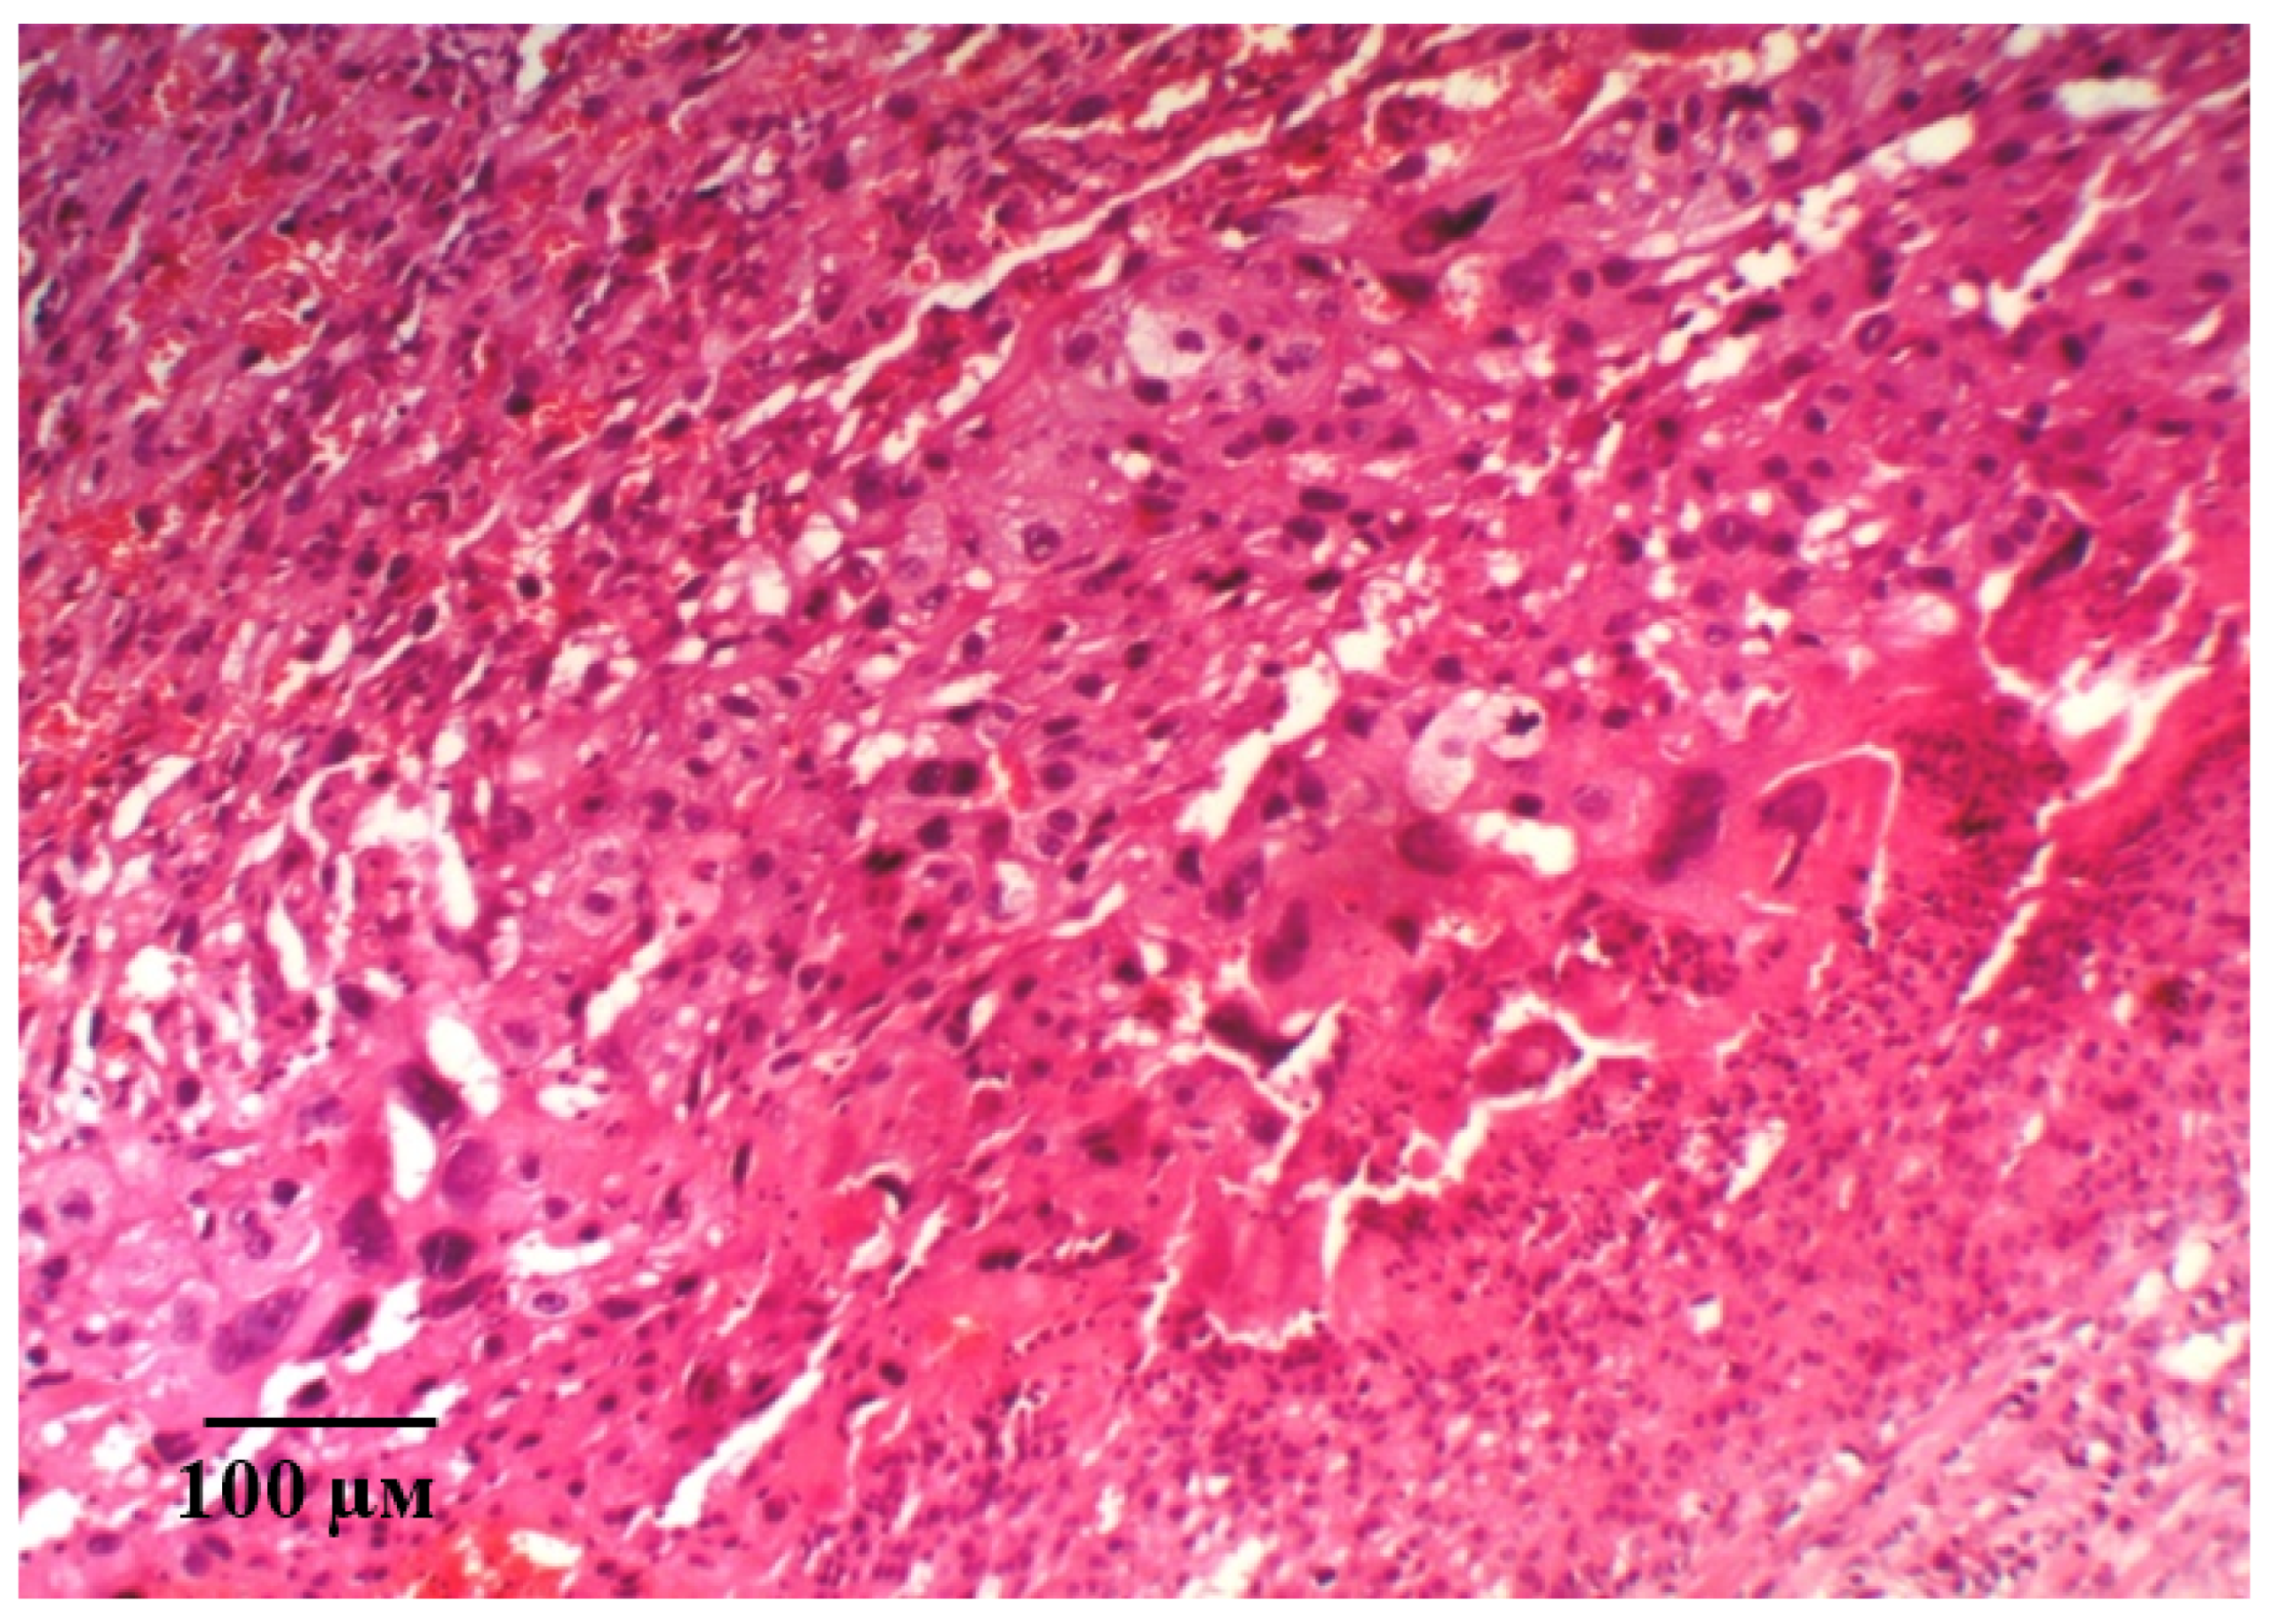

It should be noted that, in the microsections in the anchoring and terminal villi, the phenomena of angiomatosis, as well as sclerosis of their own blood vessels and the stroma of the villi were observed. The consequence of this process is a violation of histoarchitectonics and expansion of the interstitial space. In addition, in some villi, vascular thrombosis was detected, and in some villi, hemorrhages were localized both in the stroma and in the interstitial space. Deposits of fibrin filaments and elements of desquamated chorial epithelium were observed between the villi. The absence (or in a few cases) of syncytial capillary membranes and syncytial knots should be noted. This reaction is compensatory and adaptive in nature, aimed at eliminating violations and resuscitation the volume of microcirculation. It should be noted that, in the giant cell trophoblast, namely, in the visualized decidual membrane of the maternal placenta, inflammatory and dystrophic changes are pronounced. Optically empty decidual cells are determined against the background of cells with absolutely integrity structures (Figure 8A). The structure of the morphological elements is broken. Extensive focal fields of necrosis and fibrin deposits are in the field of view (Figure 8B). There is a pronounced deformation of decidual cells.

Figure 8.

Microphotographs of the maternal placenta on the 21st day of gestation in control animals with ADMA-like preeclampsia. Note: Impaired structure of morphological elements of the placenta. Optically empty decidual cells (A). Extensive fields of necrosis and fibrin deposits (B). Hematoxylin and eosin staining. Magnification: 400× (A,B).